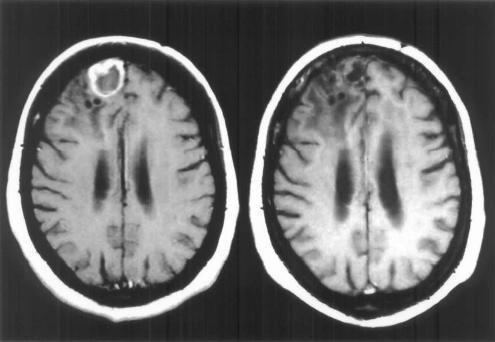

II级星形细胞瘤的特征是细胞过多,并弥漫性浸润到周围的脑实质中。通常无法实现对II级肿瘤的完全手术切除。患有II级星形细胞瘤的患者的中位生存期为5至8年。II级星形细胞瘤患者的中位生存期从1999-2001年的44个月增加到2005-2007年的57个月。在2008-2010年期间,II级星形细胞瘤的存活功能未达到50%。